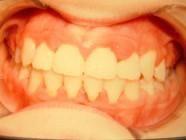

1η περίπτωση

Αρχική οδοντοσκελετική κατάσταση παιδιού με προγναθισμό άνω γνάθου και έντονη οριζόντια πρόταξη άνω τομέων Η σημασία της στοματικής υγιεινής και ορθοδοντικής

027 Αμέσως μετά το τέλος της ορθοδοντικής θεραπείας. Οι αλλαγές στην οδοντική του σύγκλειση αλλά και στο πρόσωπο είναι εμφανείς 15 χρόνια μετά την αρχική περάτωση της θεραπείας, το αποτέλεσμα παραμένει σταθερό και ο ασθενής απέκτησε ένα υγιές και αρμονικό χαμόγελο και πρόσωπο. Η σημασία της στοματικής υγιεινής και ορθοδοντικής πρόληψης